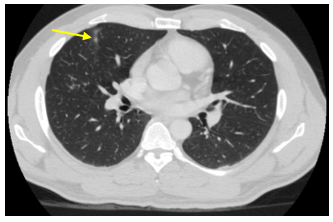

Chụp cắt lớp vi tính lồng ngực: Hình ảnh các nốt kính mờ rãnh liên thùy và màng phổi phải kích thước 2x3mm. Đám dải xẹp phổi thùy giữa phổi phải

Hình 6: Hình ảnh chụp cắt lớp vi tính lồng ngực: nốt tổn thương u phổi phải nhỏ hơn ban đầu sau 3 tháng điều trị (mũi tên vàng)

Đánh giá: Bệnh đáp ứng 1 phần

Điều trị tiếp: Alectinib 600mg/lần x 2 lần/ngày,uống trong bữa ăn